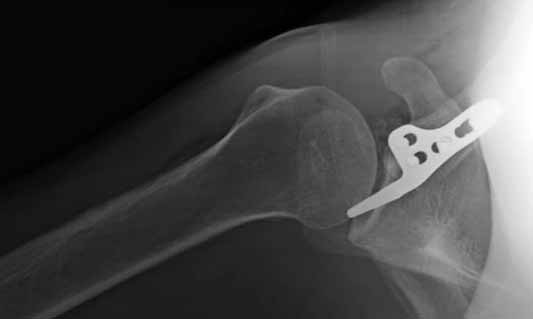

Re: ключичная пластинка

Отправитель: Серж 24 Июнь 2011, 13:43

|

foto 4

4.JPG

14KB (14434 bytes)

Отправитель: Серж 24 Июнь 2011, 13:45

foto 5

коллаж у меня не получился, пришлось отдельно рентгенограммы присоединить :-))

5.JPG

15KB (16356 bytes)

Замечание понял, спасибо и нормальные рентгенограммы, молодец!

Во вторых, это хорошо что нашли длинную пластину, я об этом писал "пластина короткая, не покрывает медиальный диафизарный фрагмент ключицы", и у нас не получилось, пластина не выдержала...

Мне кажется что если понять принципы, то можно использовать и короткую пластину. Что мы с успехом применяли раньше и применяем сейчас, но уже более осознанно. В вашем случае Серж, у меня стойкое ощущение, что необходима дополнительная иммобилизация, так как неправильно выбрано место введения крючка и при ранней нагрузке пластину просто вырвет. Если вам несложно не могли бы вы продемонстрировать прямую и боковую проекцию и в более хорошем качестве. ИМХО

Теоретически можно использовать и короткую пластину. Но на операции дистальный отломок( акромиальный конец ключицы ) был коротким и оскольчатым, поэтому крючок и использование там блокированных винтов в пластине было очень уместно. Доступ - "сабельный удар". Точка введения крючка - сразу сзади от ключично-акромиального сустава. Если честно - больше внимания уделяли репозиции отломков и адекватному расположению пластины на ключице :-) крючок проверяли на прочность фиксации за акромион и полный объем движений в плечевом суставе. После операции рука на косынке, нагрузку ограничили. Снимки есть в нормальном разрешении, но здесь "размер файла не превышал 75 кб." Если есть необходимость залью в пикассу...